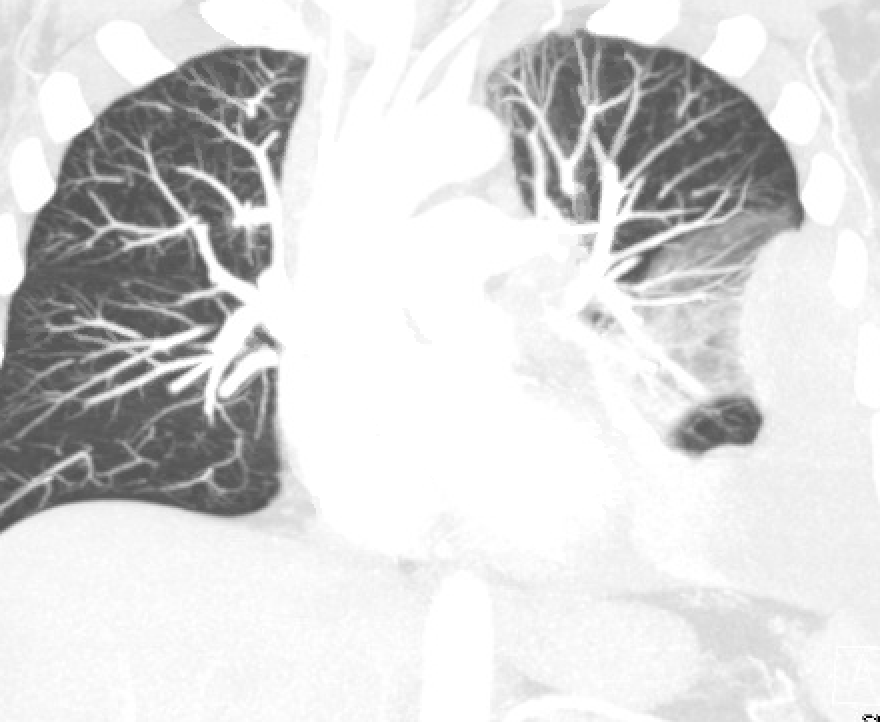

While waiting impatiently for CXR, let's look back at a prior CT. Notice the large mass in the middle of the left lung.